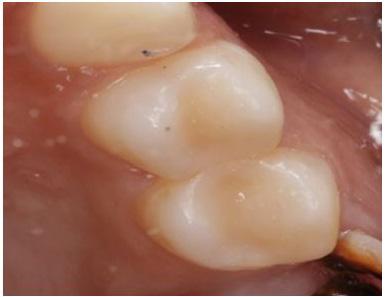

A patient came to the practice after a prolonged period without visiting a dentist. The patient reported intense pain in the upper left premolar, particularly in response to cold and heat, and also experienced spontaneous pain. After a comprehensive examination, various treatment options were discussed with the patient. Due to the severe pain, the patient opted to begin with the treatment for the second premolar.

Clinical Examination

Upon clinical examination, caries were diagnosed in the distal area of tooth #24, and a deep caries lesion in the mesial area of tooth #25 was found to be causing irreversible pulpitis. In tooth #26, only a root remnant was present, and an extraction was planned. (Fig. 1 & 2)

The root canal treatment was successfully completed,and the patient reported relief from the spontaneous pain. (Fig. 5&6).